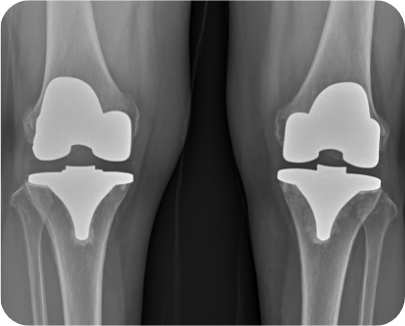

무릎인공관절 전치환술 사례1

• ▲ 수술 전

• ▲ 수술 후

무릎인공관절 전치환술 사례2

▲ 무릎인공관절 부분치환술 후

• 2) 무릎인공관절 전치환술

무릎의 앞쪽에 10~12cm의 절개를 넣고 무릎 관절 전체를 노출시킨 상태에서 대퇴원위부 및 경골 고평부에 각 뼈의 축에 맞추어 손상된 관절부분을 절제한 후 정해진 기구를 삽입하여 움직임 및 체중부하, 정렬 등에 이상이 없게 만듭니다.